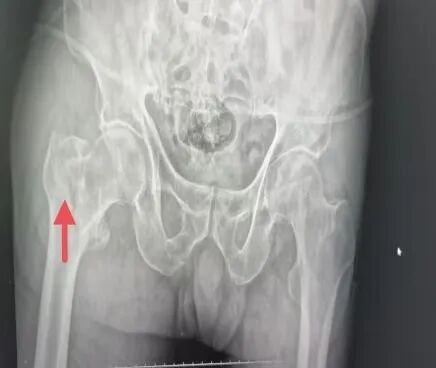

“转花骨”骨折在临床叫股骨粗隆间骨折,又称“股骨转子间骨折”,指发生于髋关节囊线以外至小转子下方区域内的骨折。

图片图片

2.直接暴力或间接暴力均可引起骨折,而最常见的原因是跌倒,髋部直接着地,大部分老年人比较瘦弱,髋部骨头紧邻皮下,无缓冲作用,加上老年人合并骨质疏松,当下肢突然扭转、跌倒、轻微的外力即可以引起该处骨折。股骨转子间骨折保守治疗时间长,需长期卧床,并发症发生率高,伤后第1年死亡率高达23%~34%。因此又被称作“人生最后一次骨折”。